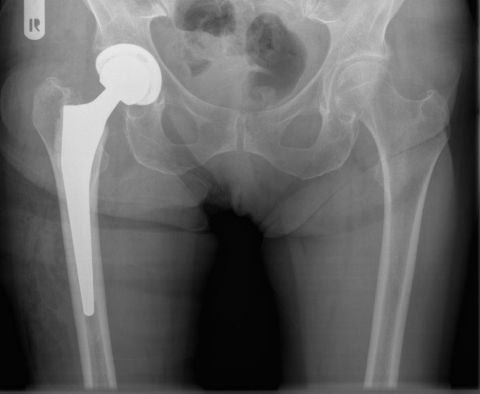

DIE FOLGENDEN BILDER ZEIGEN BEISPIELHAFT RÖNTGENERGEBNISSE NACH OPERATIVER BEHANDLUNG IN UNSERER ABTEILUNG:

Künstliches Hüftgelenk bei instabilen und verschobenen Brüchen

03/2021 – 76 jährige Frau mit wahrscheinlich durch Osteoporose bedingtem Bruch des Schenkelhalses rechts. Es wurde ein zementierter Standardschaft verwendet, der eine gleichmäßige Krafteinleitung in den Knochen des Oberschenkels gewährleistet.  Verlauf sonst unkompliziert mit guter Gelenkfunktion bereits 2 Monate nach Operation. Die Osteoporose sollte durch Bewegung und Medikamente über einen längeren Zeitraum behandelt werden.

OPERATIVE VERSORGUNG DER PATIENTIN